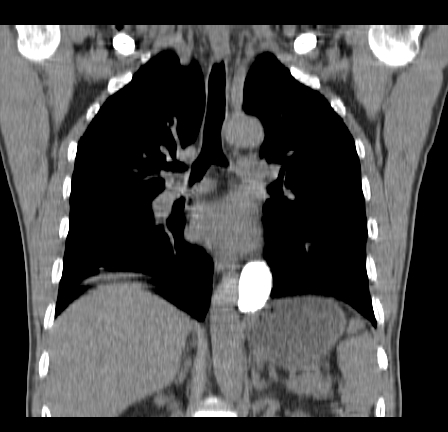

以下是引用影像孺子牛在2009-5-20 23:18:00的发言:[br]左侧后心膈角处类椭圆形钙化灶,最常见的是淋巴结钙化,但太大了不支持,其它如食管囊肿钙化、实性畸胆瘤等。何东西钙化真不好定。

以下是引用zbp537在2009-5-20 20:52:00的发言:[br]钙化灶,来源不好说。